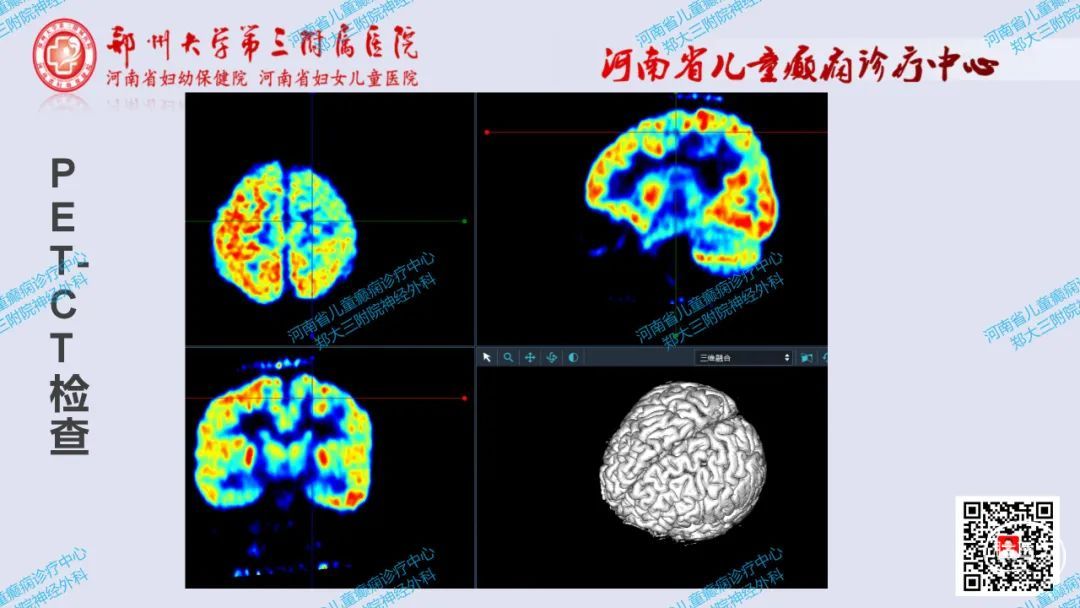

《术战癫峰》第68期:左额上沟发育异常导致癫痫行手术切除一例

郑大三附院神经外科